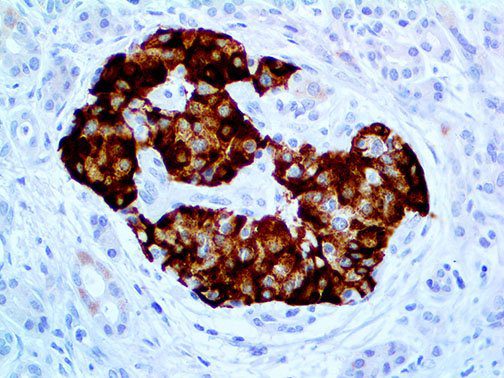

The first cytokines released are interleukin 1β (IL-1β) and tumor necrosis factor-α (TNF-α), which attract a variety of circulating white blood cells (WBCs) to the infection site, including neutrophils, monocytes, macrophages, and natural killer (NK) cells. This response, along with the antipathogenic chemicals released by these cells (i.e., complement), comprise the innate immune response. These cells directly attack the invading pathogen and also release additional cytokines, chief among them interleukin-1 and 6 (IL-6). IL-6 is essential for invoking the adaptive immune response, which calls T-cells, B-cells, and T helper (Th) cells to the infection site. IL-6 also stimulates further recruitment, proliferation and activation of macrophages.

It is the ICU physician who is most likely to witness one of the deadliest manifestations of the abnormal immunological response, the cytokine storm syndrome (CSS). This response is also referred to by some as the cytokine release syndrome (CRS). CSS is characterized by continuous activation and expansion of macrophage and lymphocyte populations, which secrete large amounts of cytokines, causing the cytokine storm. This massive cytokine release is akin to hemophagocytic lymphohistiocytosis (HLH) disease, a syndrome characterized by initial unchecked and persistent activation of cytotoxic T lymphocytes and NK cells.